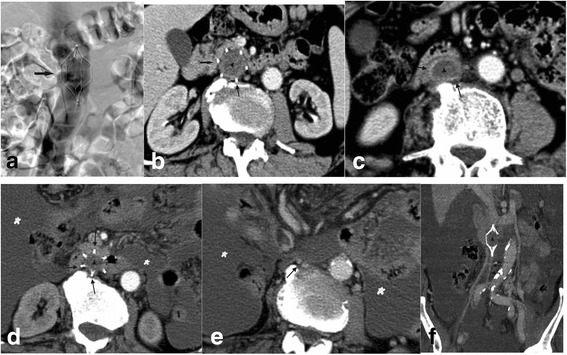

Fig. 2.

A case of traumatic intracranial bleeding from a left-sided iliofemoral thrombosis. a–c Follow-up CT of the IVC was obtained 10 days after filter placement. Note the extensive thrombosis (asterisks) in the IVC below the filter and the thickened IVC wall (black arrows) (b). The black arrow (b) marks the tip of the filter. d–g The last CT imaging of the IVC was performed outside the IVC shows one of the struts eroding the lumbar body, exhibiting grade 3 protrusion. The IVC has atrophied below the filter (e, f). Arrow in D marks the tip of the filter. Double white arrows in E mark the IVC as a strip below the filter. The reconstructed CT imaging (g) shows a fractured strut of the filter (black arrow)